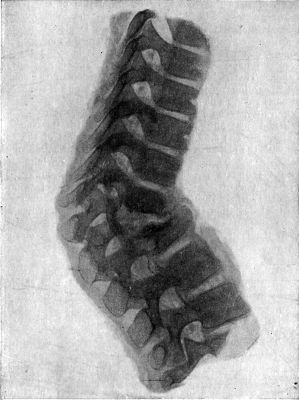

| 212. | Radiogram of Museum Specimen of Pott's Disease in a Child | 435 |

| 210. | Tuberculous Osteomyelitis affecting several Vertebræ at Thoracico-Lumbar Junction | 432 |